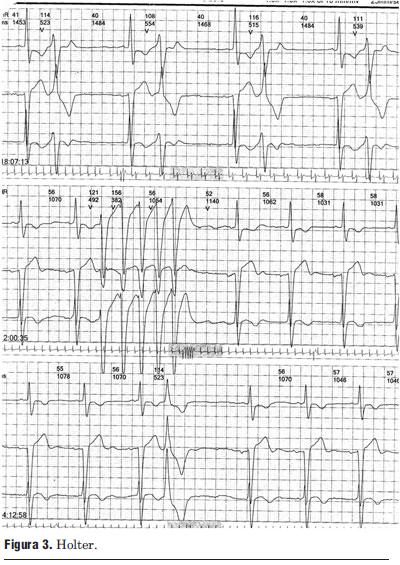

Paciente de 69 años de edad, sexo masculino, procedente del departamento de Tacuarembó. Ingresa al centro de tratamiento intensivo del Hospital de Tacuarembó el día 1º de febrero de 2010. Había consultado horas antes por episodio sincopal constatándose una taquicardia regular de complejos QRS anchos (figuras 1A y 1B), hipotensión arterial y mala perfusión periférica; es medicado inicialmente con adenosina intravenosa, sin respuesta; se resuelve cardiovertir eléctricamente; al administrar propofol i/v revierte espontáneamente a ritmo sinusal.

Figura 1A. Taquicardia ventricular clínica, hasta V2. Registro en servicio de emergencia.

Figura 1B. Taquicardia ventricular clínica. V3 a V6.